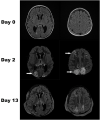

Posterior reversible encephalopathy syndrome and necrotizing enterocolitis in a pediatric patient with medulloblastoma and COVID-19 infection